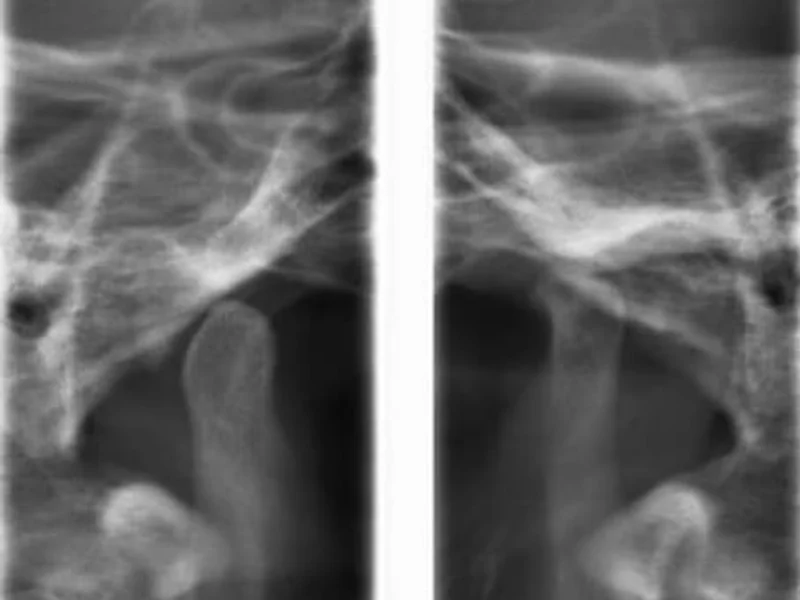

Snimanje digitalnih ortopana, pojedinačnih zuba, sinusa i temporomandibularnog zgloba u Vukovaru.

- –Snimka TMZ

Snimka TMZ

25 € po jedinici